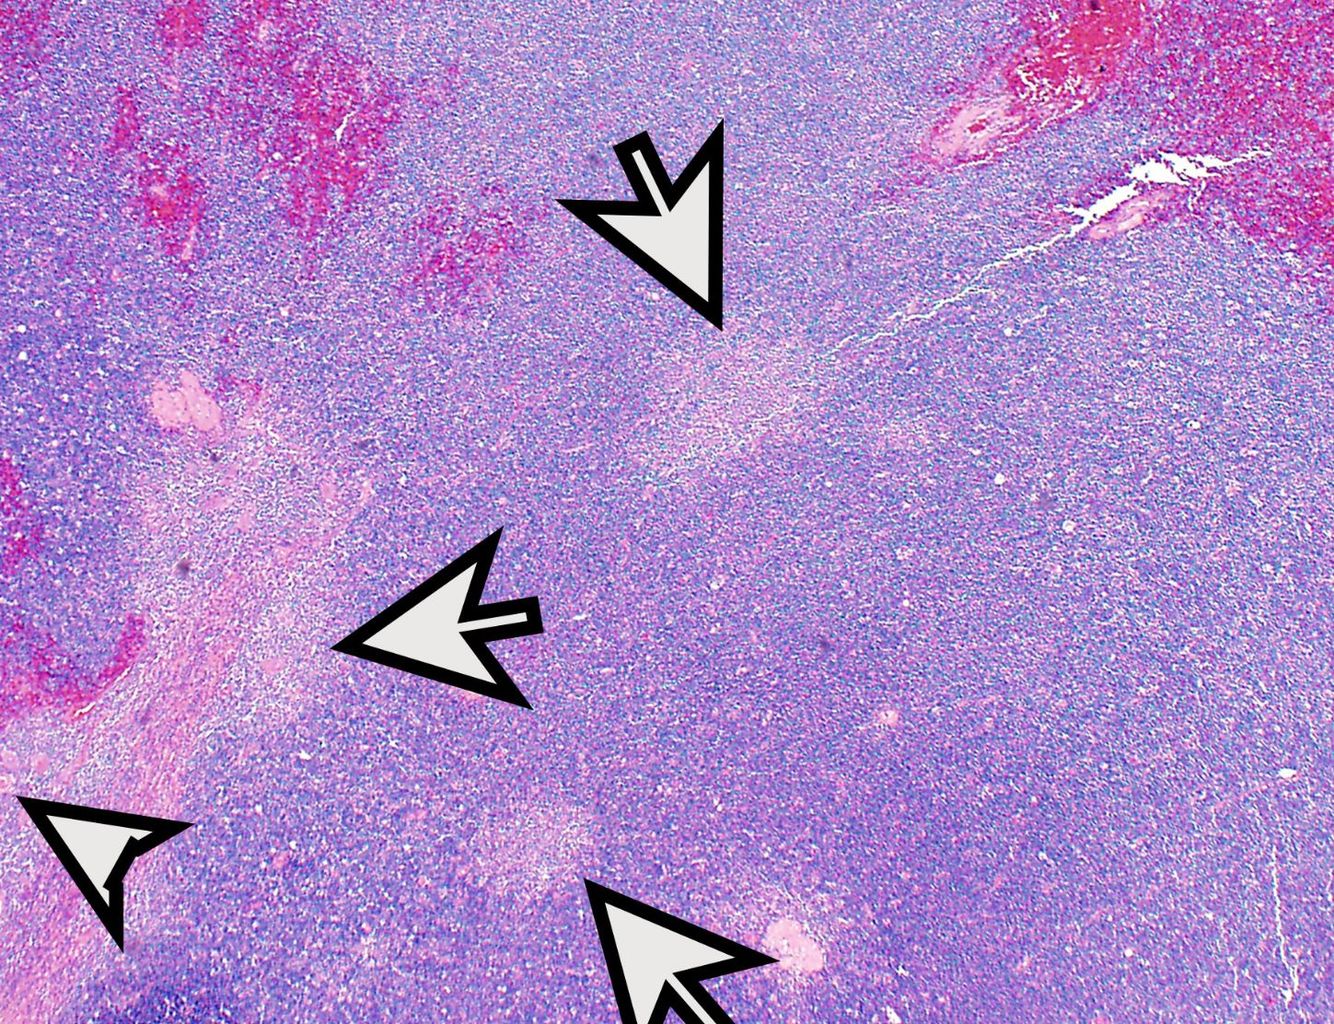

Thymoma, type B1

Type B1 thymomas are lymphocyte rich. They look the closest of all thymoma subtypes to regular thymoma, but are large and hypercellular, and whatever epithelial elements are left will be floating in a sea of lymphocytes.

If you see a true Hassall corpuscle, it is type B1 (or AB if there is an A component). But more often, you will just see “medullary islands” of epithelial differentiation that stain p40 and keratin positive. TdT stain will highlight the thymocytes and is very useful for picking out the nonstaining epithelial islands.